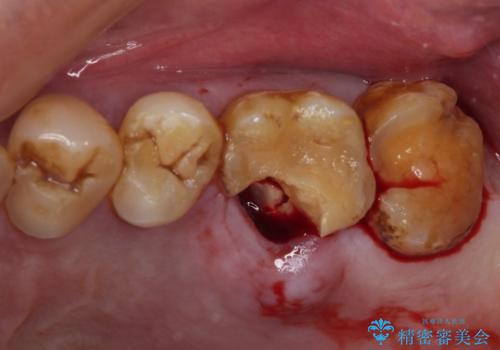

咬合面に大きな修復物が入っており、その境目から破折し、歯肉の内側の歯根にまで破折が及んでいました。

残念ながら神経組織が露出しており、根管治療が必要となっていたため、まずは根管治療を行うこととしました。

根管治療後に、歯根にまで及んでしまった破折部分を適切な位置に変更するため、歯槽骨の削除を伴う外科処置を行い、その後補綴治療を行うこととしました。